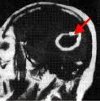

Пункция абсцесса мозга. Диагностическая операция, при которой жидкость извлекается из полости абсцесса для дальнейшего исследования. Операция назначена для уточнения диагноза, изучения содержимого абсцесса, определения типа микроорганизмов, вызвавших инфекцию. Кроме того, методика используется для введения контрастного вещества и последующего изучения патологического образования с целью выяснения его границ. Результаты пункции абсцесса головного мозга необходимы для точной диагностики заболевания и выбора эффективной тактики лечения.

Если есть подозрение на абсцесс мозга, невролог может выполнить пункцию для уточнения диагноза, дифференцирования абсцесса от разлагающейся опухоли, гематомы, демиелинизации, гранулемы или кисты. В клинической неврологии пункция абсцесса также проводится для введения контрастного вещества и последующего магнитного резонанса, что позволяет точно определить местоположение патологического очага, его границы, наличие капсулы или ее разрыв с проникновение гноя в окружающие ткани. Эти данные имеют большое значение для выбора тактики лечения и планирования операции. Изучение содержимого абсцесса, полученного после пункции, позволяет выявить патогенные микроорганизмы, которые вызвали гнойные состояния, и назначить лечение на основе их чувствительности к антибиотикам. Если диагноз подтверждается в процессе манипуляции, можно выполнить одноэтапное измерение: удаление гноя и введение препарата в полость абсцесса.